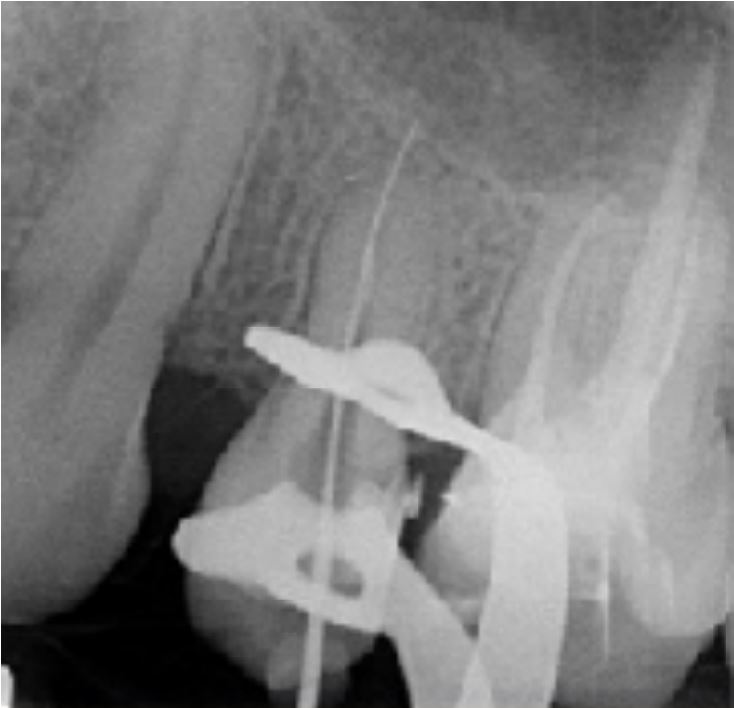

Cas clinique n°1

Dr Hetzel Rémy (Bourgoin Jallieu)

"Traitement prémolaire avec racine courte"

Historique

Dent ouverte aux urgences - milieu hospitalier

passage de lime manuelle K20 très facilement au-delà de l'apex

suspicion de diamètre apical non respecté

pris d'un premier cliché avec lime manuelle K25

Radio per-opératoire

Passage de séries séquentielles de limes manuelles et prise de longueur de travail avec lime K20

Longueur de travail déterminée à 17.5mm

Lime apicale maitresse de 30/100ème

Alésage à l'aide de la séquence Fanta ROTARY jusqu'à la lime 30/04%